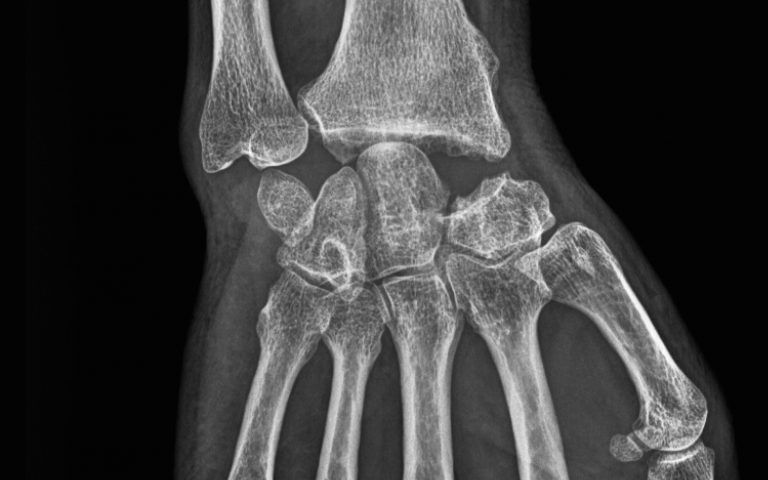

Pathologies de la Main et du poignet Polyarthrite rhumatoïde

Polyarthrite rhumatoïde